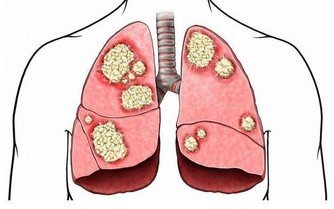

05.纖維攝入不足

充足的膳食纖維能夠促進腸道蠕動和吸水膨脹,防止便秘,縮短有害物質在腸道的停留時間,有助於預防和降低腸癌發生率。